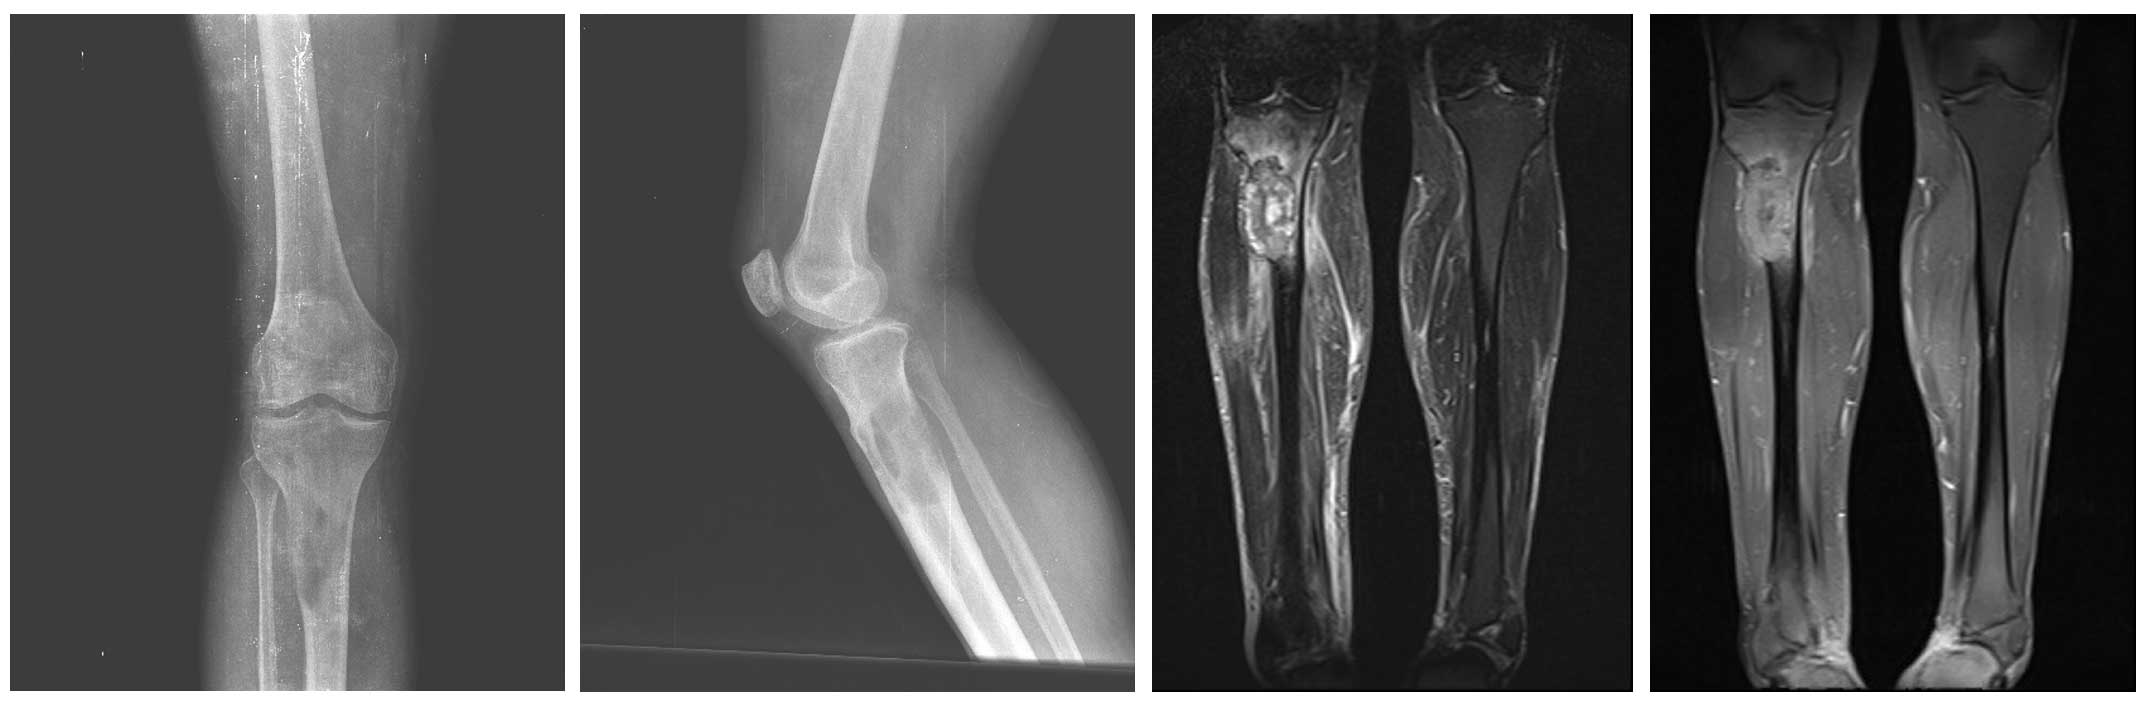

Görüntülemelerde proksimal tibia metastazı saptanmış ve kırık riski yüksek

Proksimal tibia kemiğinde özefagus kanseri metastazına bağlı patolojik kırık riski

Ameliyat Öncesi: Röntgende tibia üst uçta metastaza bağlı kemik yıkımı ve kırık riski, MR’da tümörün kemiğin dışına çıktığı ve yaygın ödem varlığı görülmekte.